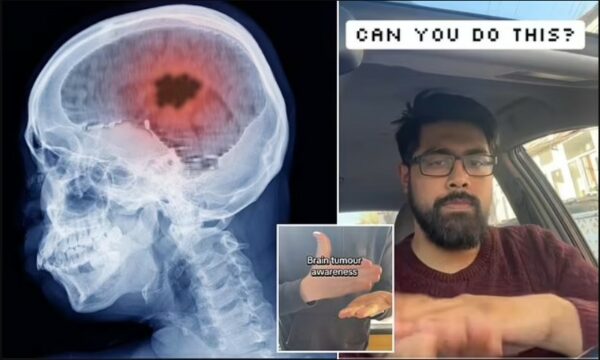

Test i thjeshtë me gishta që mund të zbulojë rrezikun për një sëmundje të frikshme të mushkërive

Mjeku demonstron testin 30-sekondësh me duar që mund të zbulojë nëse keni një tumor në tru